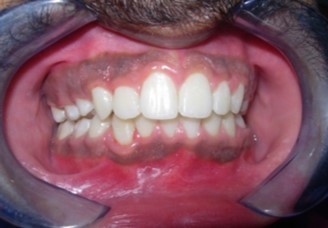

The soft tissue frontal and profile improved dramatically. (Figure 7a-b). The bilateral posterior crossbite was corrected. The severe increase in overjet of about 13mm was effectively reduced to 3mm and the severe deep bite was also corrected (Figure 7c,Figure 7d). Fixed maxillary and mandibular lingual retainers were given. (Figure 7e, Figure 7f). Post orthodontic treatment, normal root inclinations of the teeth and normal alveolar bone levels was observed. (Figure 8).

Figure 7c.Post-treatment intra-oral-Frontal

Figure 7d.Post treatment intra-oral – Right

The end of treatment result showed a good improvement in the transverse, anteroposterior, and vertical dimensions with markedly improved dentofacial esthetics.

A combination therapy of a banded rapid palatal expansion appliance and orthodontic treatment with pre adjusted edgewise appliance therapy was instrumental in the correction of a severe skeletal Class II malocclusion with an orthognathic maxilla and retrognathic mandible. This two-phase therapy resulted in a dramatic improvement of the facial and smile esthetics with good occlusal interdigitation that enhanced the patient’s speech, personality and self-esteem.